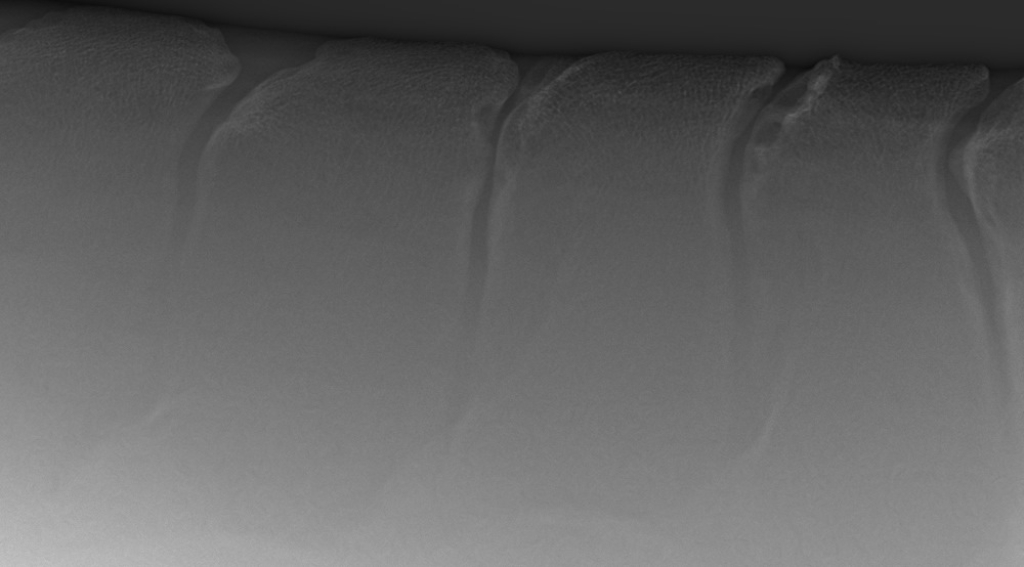

Links: Overgang van de borstwervels naar de lendenen

Rechts: Röntgenfoto van de overgang van borst- naar lendenwervels